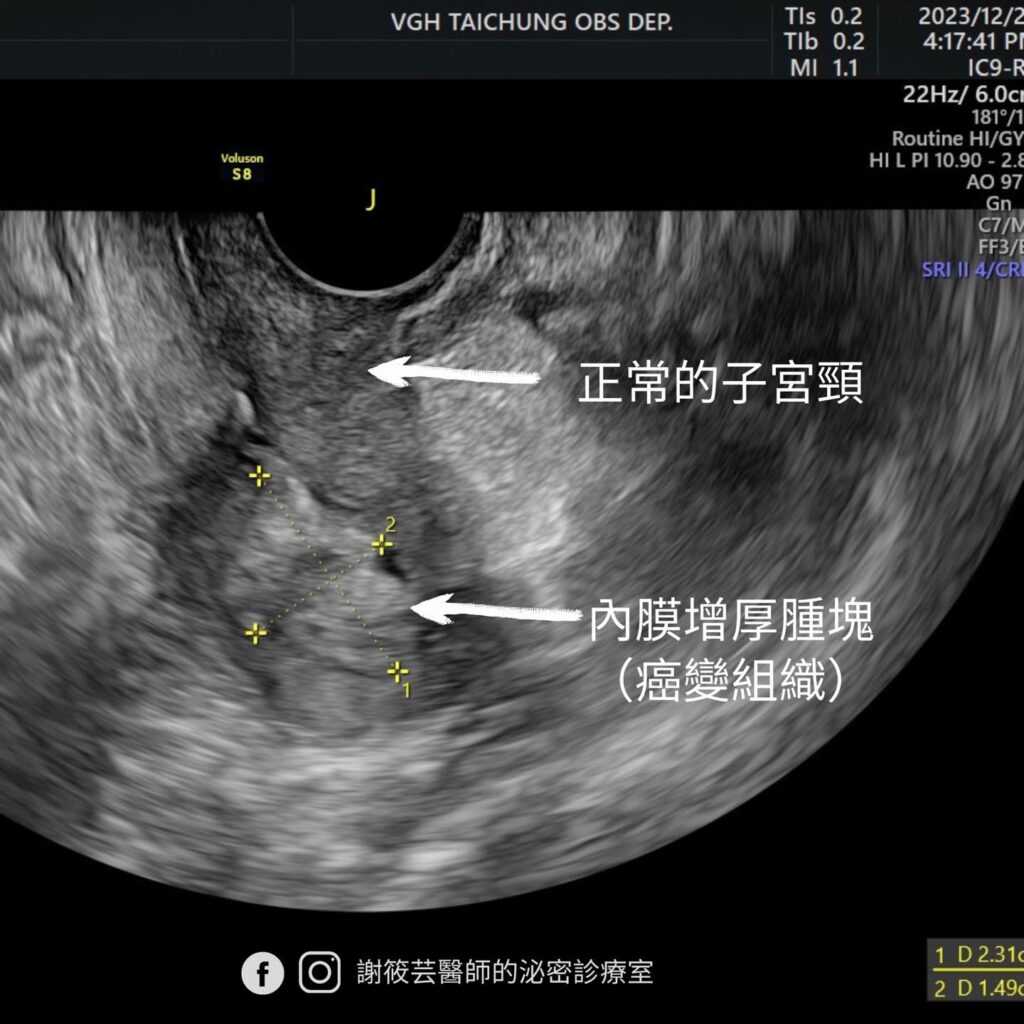

陰道超音波照出子宮內膜有明顯增厚,當下立刻做切片抽樣,診斷為子宮內膜癌。阿鑾在診間聽到報告簡直無法置信,自己一向規律作息、不菸不酒,也沒有服用荷爾蒙藥物,還有定期抹片檢查的好習慣,怎麼會突然檢查出子宮的癌症呢!?